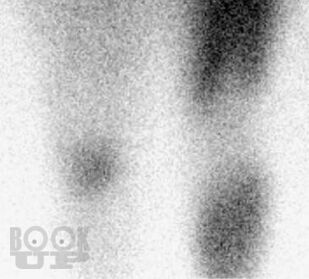

В настоящей монографии в сравнительном аспекте рассматриваются диагностические и дифференциально-диагностические возможности сцинтиграфии с неспецифическим туморотропным радиофармацевтическим препаратом и индикатором воспалительных процессов 199Tl-хлоридом. Авторами показана высокая эффективность сцинтиграфии с 199Tl-хлоридом в неспецифической индикации и дифференцильной диагностике опухолевых и воспалительных процессов опорно-двигательного аппарата, органов грудной клетки и прочих локализаций, приводятся диагностические и дифференциально-диагностические критерии этих процессов.